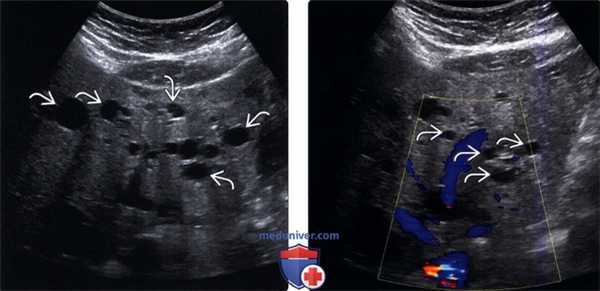

(Левый) Цветовая допплерография в поперечной проекции. Визуализируется четко отграниченная круглая киста печени, васкуляризация отсутствует, хорошо визуализируется задняя стенка га, отмечается заднее акустическое усиление, подтверждающее кистозную природу образования.

(Правый) Поперечный серошкальный УЗ срез печени. Визуализируются множественные кисты га по всей печени пациента, страдающего поликистозной болезнью печени. Заднее акустическое усиление наблюдается у каждой кисты и подтверждает кистозную природу образований. (Левый) Трансабдоминальная цветовая допплерография в косой проекции. Визуализируется кистозный абсцесс печени, окруженный гипоэхогенной паренхимой в правой доле печени. Также визуализируются внутренние перегородки и эхогенное содержимое абсцесса печени.

(Правый) Цветовая допплерография печени в поперечной проекции. В полости резекции визуализируется билома с эхогенными очагами по периферии и артефактом, вызванным хирургическими клипсами. На периферии биломы отмечается внутреннее содержимое. (Левый) Поперечный серошкальный УЗ срез печени. В правой доле печени визуализируются два прилежащих анэхогенных образования трубчатой формы с четкими границами.

(Правый) При цветовой допплерографии у этого же пациента можно отметить, что образование представляет собой сосуд, впадающий в среднюю печеночную вену. Следует всегда использовать цветовую допплерографию для оценки анэхогенных образований на предмет их возможной сосудистой природы, как в этом случае спонтанного внутрипеченочного портокавального шунта.